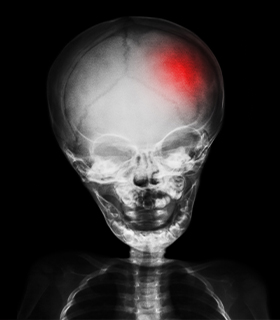

Traumatic Brain Injury (TBI) Surgery

Surgery removes life-threatening clots, hematomas, and skull fractures to treat severe head injuries, enhancing recovery and function.

Emergency and planned surgeries to address damage caused by traumatic brain injuries, enhancing recovery and function.